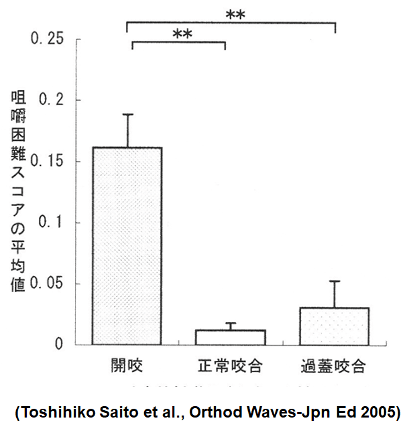

開咬はタ行やサ行の発音が適切にできず、発音障害につながることがあると報告されています。

(正常な咬合に比べ子音に3.7倍問題/Laine T. et al Eur J Orthod. 1992)